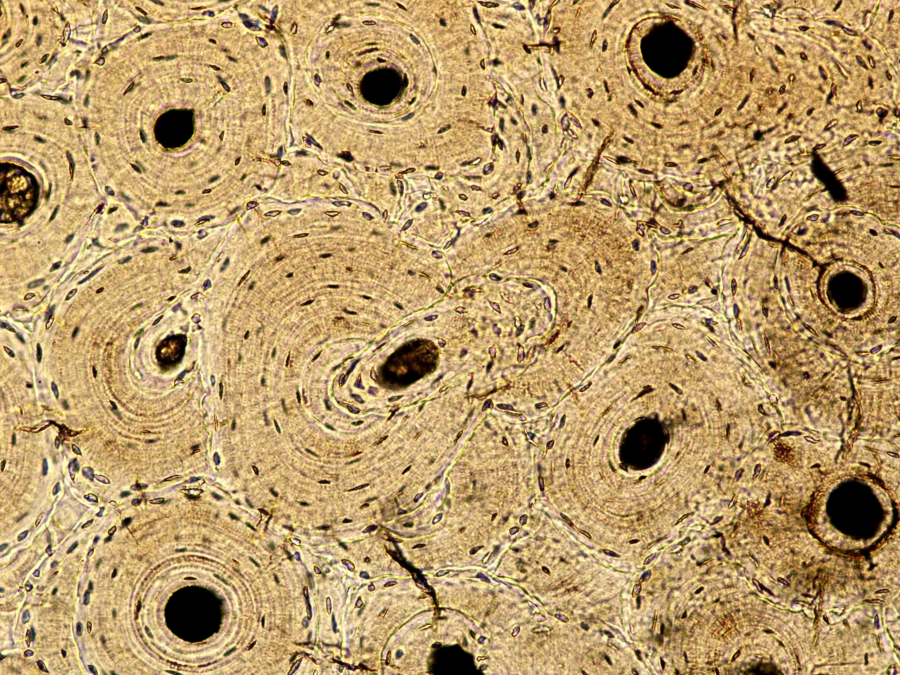

Image Filename: 56233_192-2

56233_192-2

container invno 56233

specimen id 192